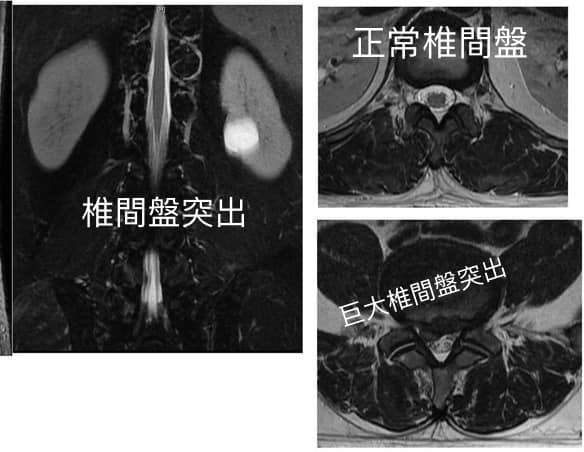

#腰椎間盤巨大突出脫垂

❗️艱難任務巨大椎間盤突出

✳️後話:為什麼有些椎間盤突出患者,情況嚴重,但經過保守治療卻「不治而愈」?並且經過核磁共振圖像顯示:既往突出的髓核還被吸收了?這到底是怎麼回事?

❇️研究發現,單純機械性壓迫神經,不會引起神經根疼痛,但是突出的髓核可誘發免疫和炎症反應,說明腰椎間盤突出症的症狀與炎症密切相關,髓核的突出誘發的免疫反應可促使突出的髓核吸收,因此在臨床上,腰椎間盤突出,尤其是脫出型(髓核游離於椎管),有自我吸收的可能性。

✅在腰椎間盤突出症初期,即發病後的前6個月是突出物自然吸收的活躍時期,且吸收程度與臨床症狀及其體徵的改善呈現相關性,經過經過多名學者追蹤觀察發現:凸型、破裂型和游離型重吸收的幾率大,存在因重吸收而致症狀緩解的可能,自行吸收或縮小的過程大多為2~6個月。